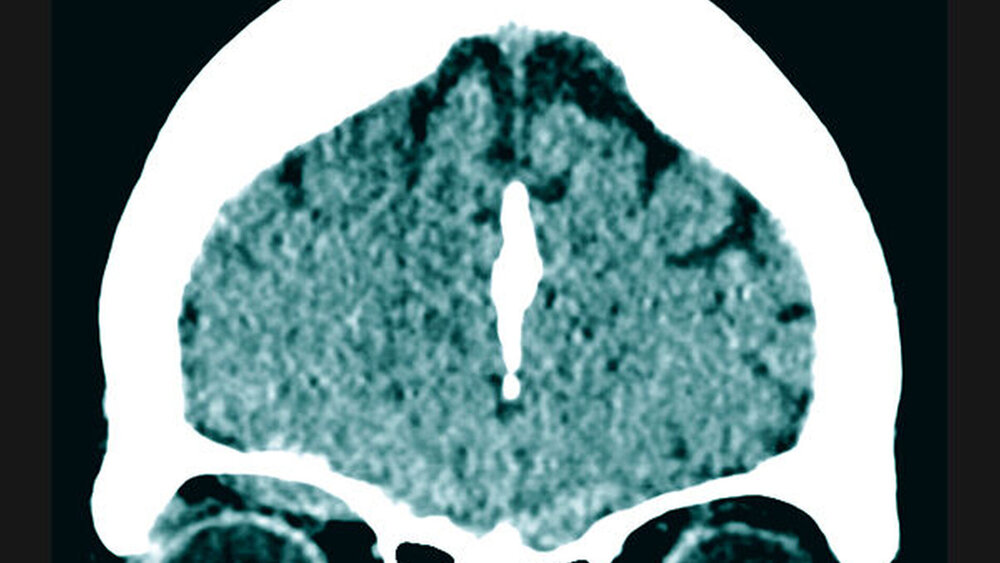

Zur weiteren Diagnostik erfolgte die Anfertigung einer Computertomografie des Schädels. Hier zeigte sich neben einem rechtsseitig temporalen Epiduralhämatom und einer Felsenbeinfraktur ein subperiostal gelegenes Orbitahämatom ohne Zeichen einer Optikuskompression (Abbildung 1). Eine Mitbeurteilung durch die ophthalmologischen Kollegen der Universitätsmedizin ergab keinen akuten Interventionsbedarf.

In der Zusammenschau der Befunde wurde sich in enger Absprache zwischen der Patientin, dem behandelnden Neurochirurgen und dem zuständigen Mund-, Kiefer- und Gesichtschirurgen zunächst für ein konservatives Therapieregime mit engmaschiger Überwachung der Glasgow-Koma-Skala, stündlichen Visuskontrollen und einer erneuten Verlaufscomputertomografie entschieden. Die Re-Computertomografie nach vier Stunden zeigte einen stabilen Befund sowohl des Epiduralhämatoms als auch des Orbitahämatoms, so dass auch nach erneuter Bildgebung und weiterhin fehlender klinischer Symptomatik der Patientin keine Indikation zu einer chirurgischen Intervention notwendig war.